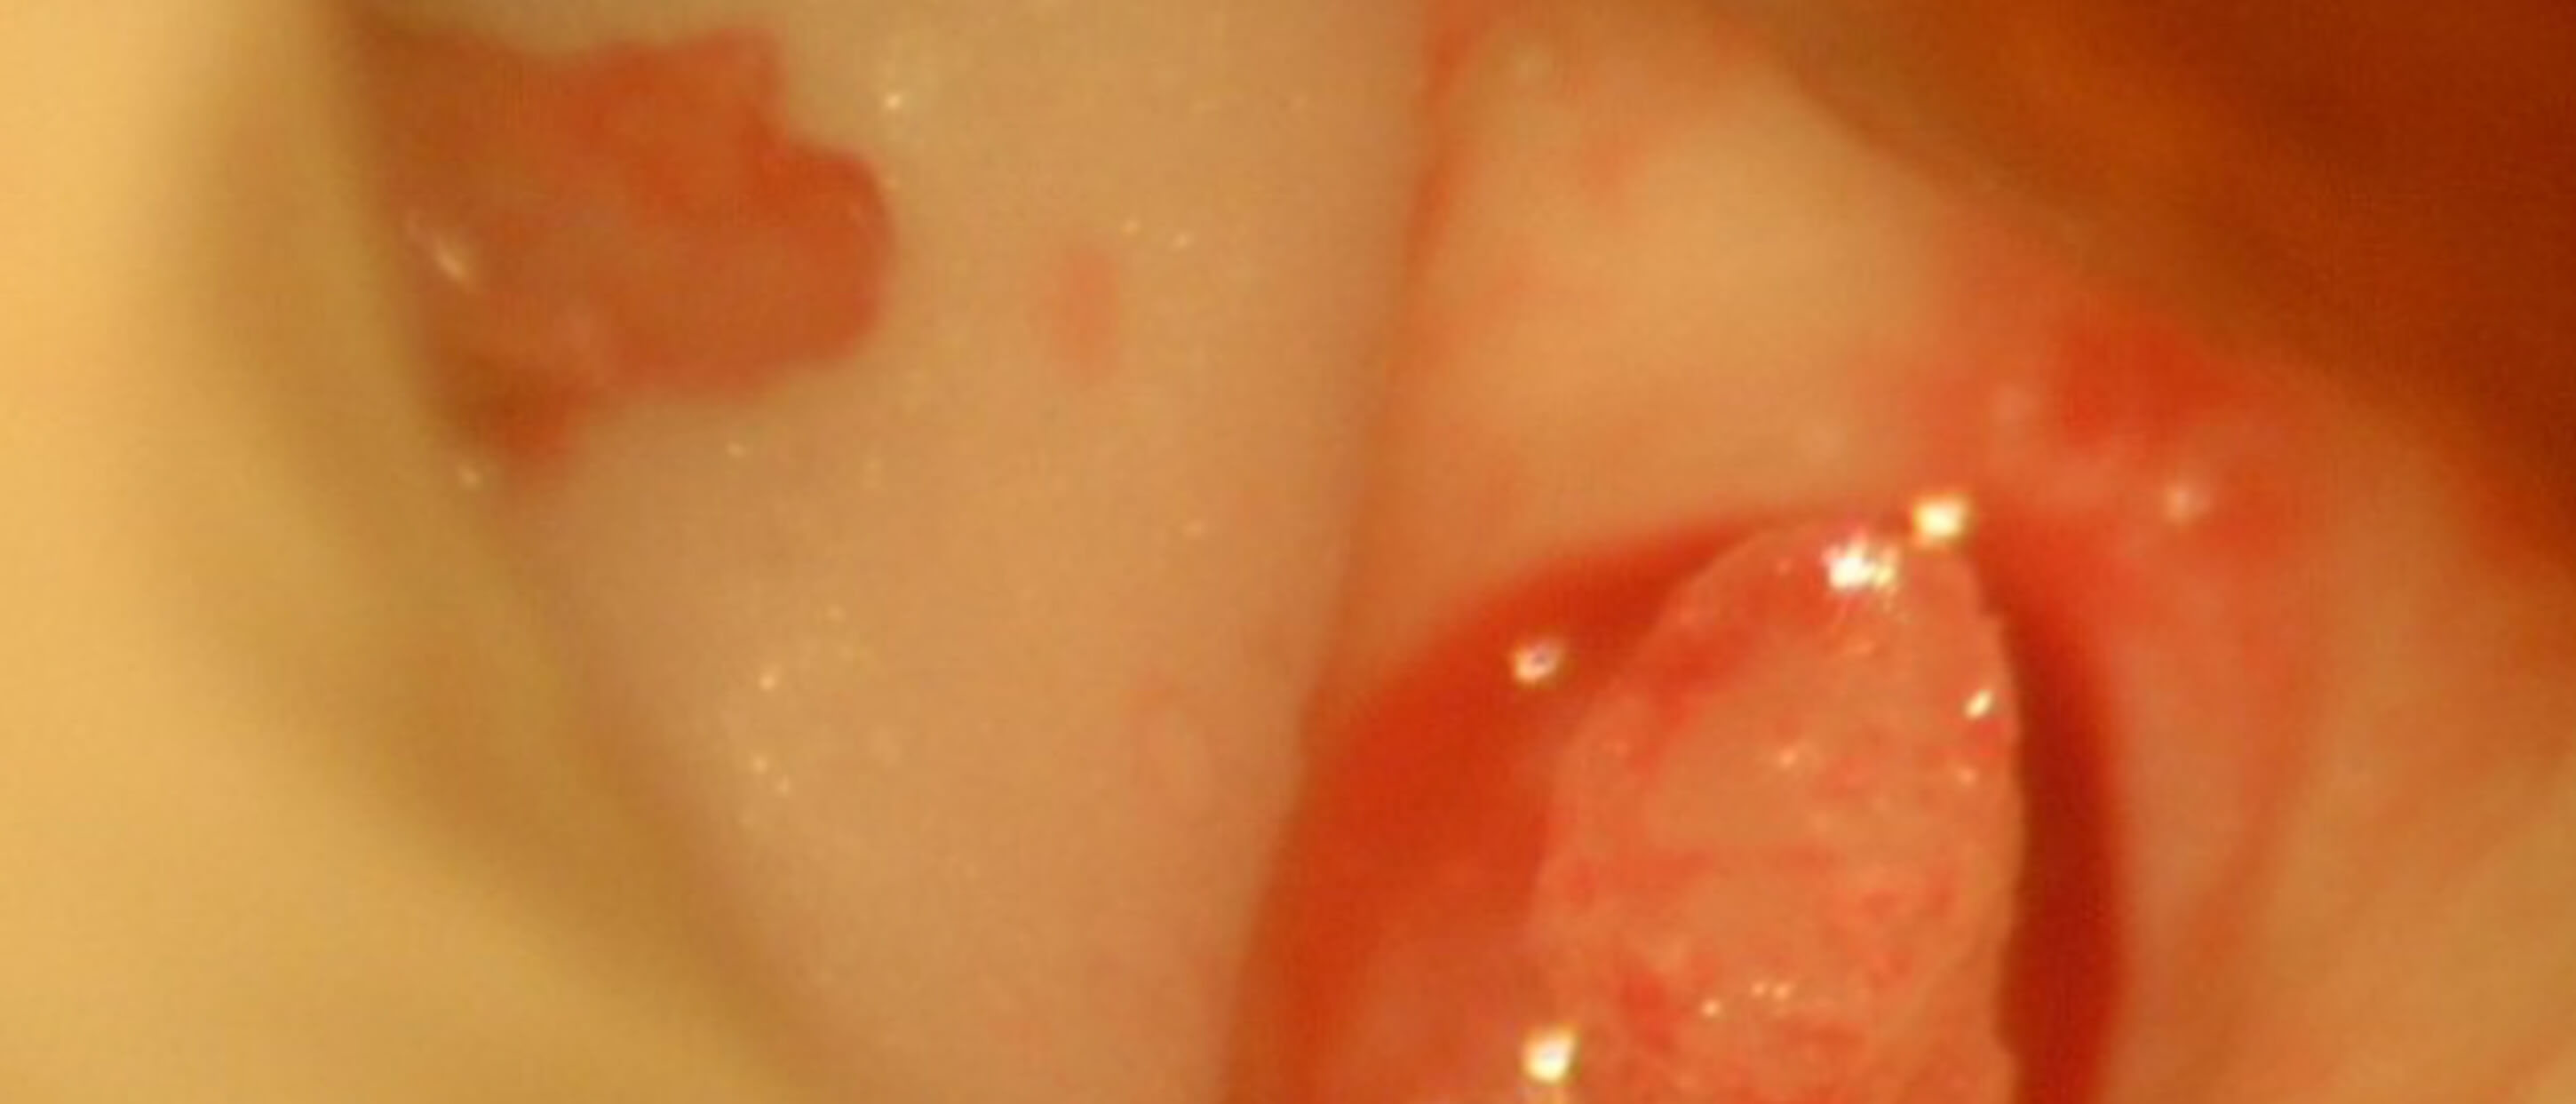

He also became aware from the recent literature that his bones had certain advantages over the newer simulation technologies in relation to the tympanic membrane, ossicles and the facial nerve. Moreover, a perforation of the tympanic membrane, or a cholesteatoma can be introduced to his bones to provide a challenge to the young surgeon.